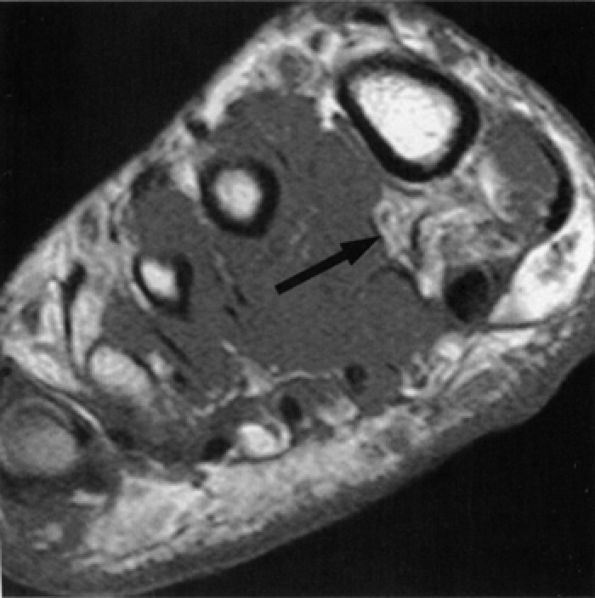

FIGURE 6.3 ● Proximal tibial entrapment in a 49-year-old patient with neuropathic foot pain. Symptoms resolved following an intra-articular steroid injection of the knee. This axial T2-weighted fat-suppressed image depicts a loose body in the popliteal muscle bursa (arrow), abutting on the neurovascular structures (arrowheads).There are many variations in muscle innervation and many communicating nerve loops in the lower extremity, particularly in the foot region.43 For example, the deep peroneal nerve may, in rare instances, supply muscles such as the adductor hallucis and flexor hallucis brevis, muscles typically innervated by the lateral and medial plantar nerves. This variability can affect the distribution of signal alterations within denervated muscles and may produce puzzling MR patterns. Familiarity with variations in innervation aids in interpreting unexpected muscle denervation signal alterations. -

Finally, the distance from the site of entrapment to the innervated muscle should be considered when searching for muscle denervation abnormalities. Proximal damage to the peroneal division of the sciatic nerve may depict denervation signal in the leg or foot. This signal alteration may be missed if only the thigh is being imaged. Similarly, MR imaging of a painful foot may overlook a more proximal entrapment in the leg or thigh (Fig. 6.3). It is important to pay careful attention to signal changes on sagittal and coronal planes, where larger portions of the limb are illustrated, to help avoid this pitfall. If the clinical suspicion for entrapment is high and no abnormalities are noted on the initial study, imaging a more distal or proximal section of the limb can also be performed.